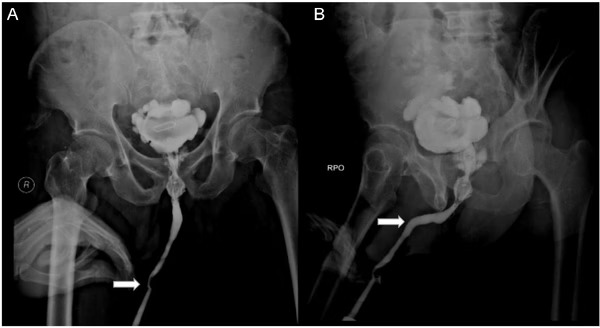

A radiografia revelou objetos estranhos, incluindo uma pedra na bexiga causada pelo objeto de metal. Durante a cirurgia, os médicos removeram uma pedra de 5×3 cm, além do cabo elétrico e uma agulha de 8 cm.

Foto: Divulgação Hospital Acadêmico Geral Soetomo

Exames posteriores mostraram complicações no ureter, com o paciente desenvolvendo hidronefrose. Os psiquiatras diagnosticaram um transtorno de adaptação, mas a causa não foi esclarecida.